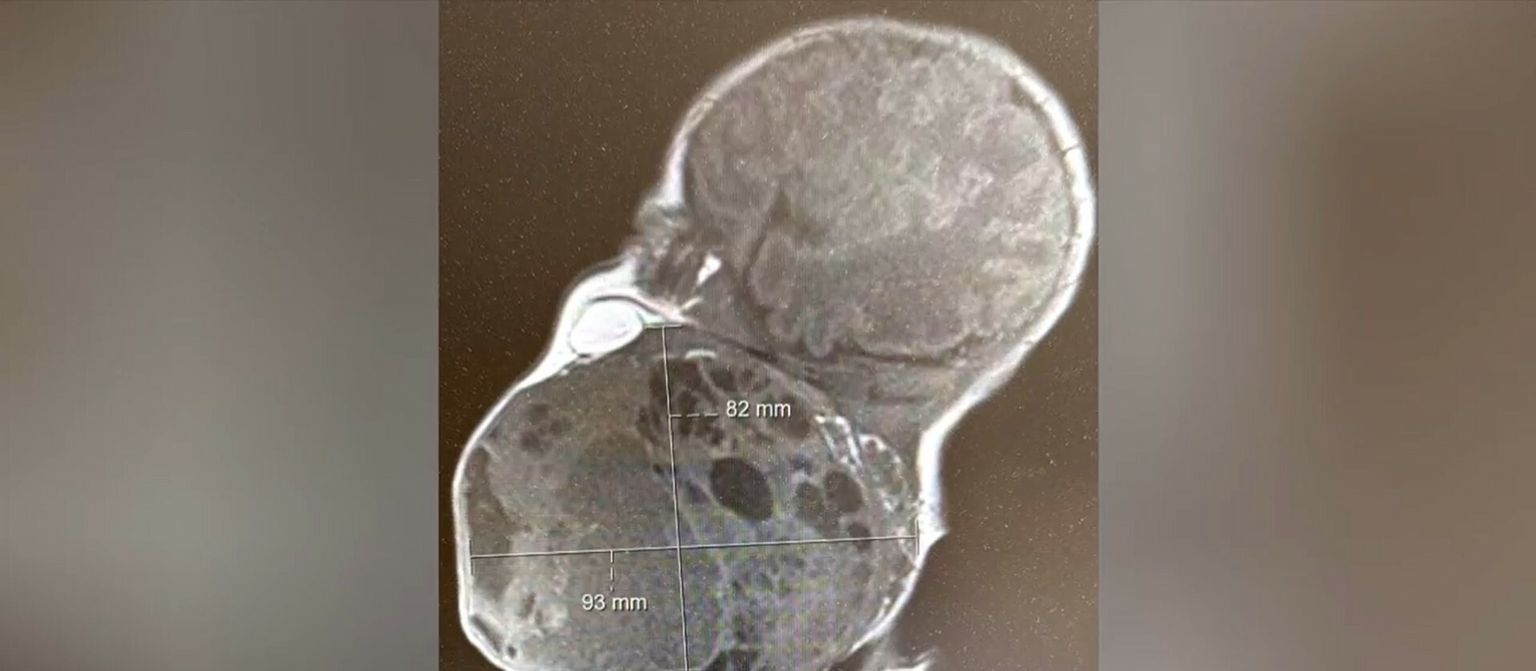

Zagrebački liječnici iznimno teškim zahvatom spasili život novorođenčeta! Majka: "Hvala dragom Bogu što ih je poslao..."

• Divna vijest iz KBC-a Zagreb - 1 Foto: DNEVNIK.hr

• Divna vijest iz KBC-a Zagreb - 2 Foto: DNEVNIK.hr

• Divna vijest iz KBC-a Zagreb - 3 Foto: DNEVNIK.hr

• Divna vijest iz KBC-a Zagreb - 4 Foto: DNEVNIK.hr

• Divna vijest iz KBC-a Zagreb - 5 Foto: DNEVNIK.hr